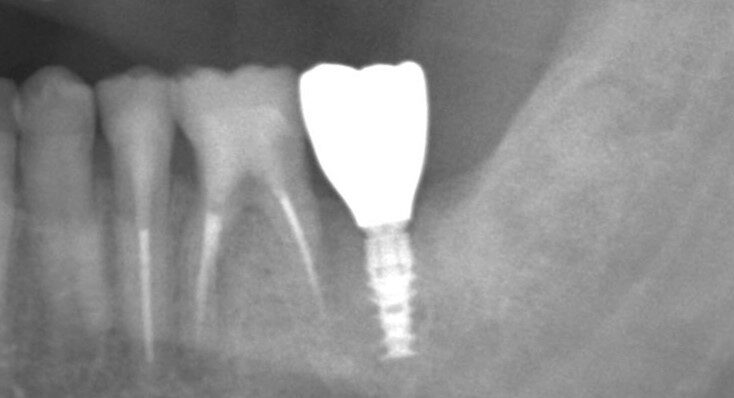

症例09

60代 男性 折れている歯を眠っている間に完全無痛でインプラントをして欲しい

歯根破折の確定診断

歯根破折の確定診断

治療後

治療後

術前レントゲン

術前レントゲン

術後レントゲン

術後レントゲン

| 主訴 |

折れている歯を眠っている間に完全無痛でインプラントをして欲しい。インプラント手術自体をいかに痛みや不安がなく治療ができる医院がないかを探していた。抜歯と同日のインプラント手術を「完璧にできる」という歯科医師に治療してもらいたいと思っている。 |

|---|---|

| 年代・性別 | 60代 男性 |

| 治療部位 | 左下7 |

| 治療費用 |

インプラント手術料 300,000円 |

| 手術回数 | 2回 |

| 治療期間 | 4ヶ月 |

| 手術時間 | 90分 |

| 治療回数 | 5回 |